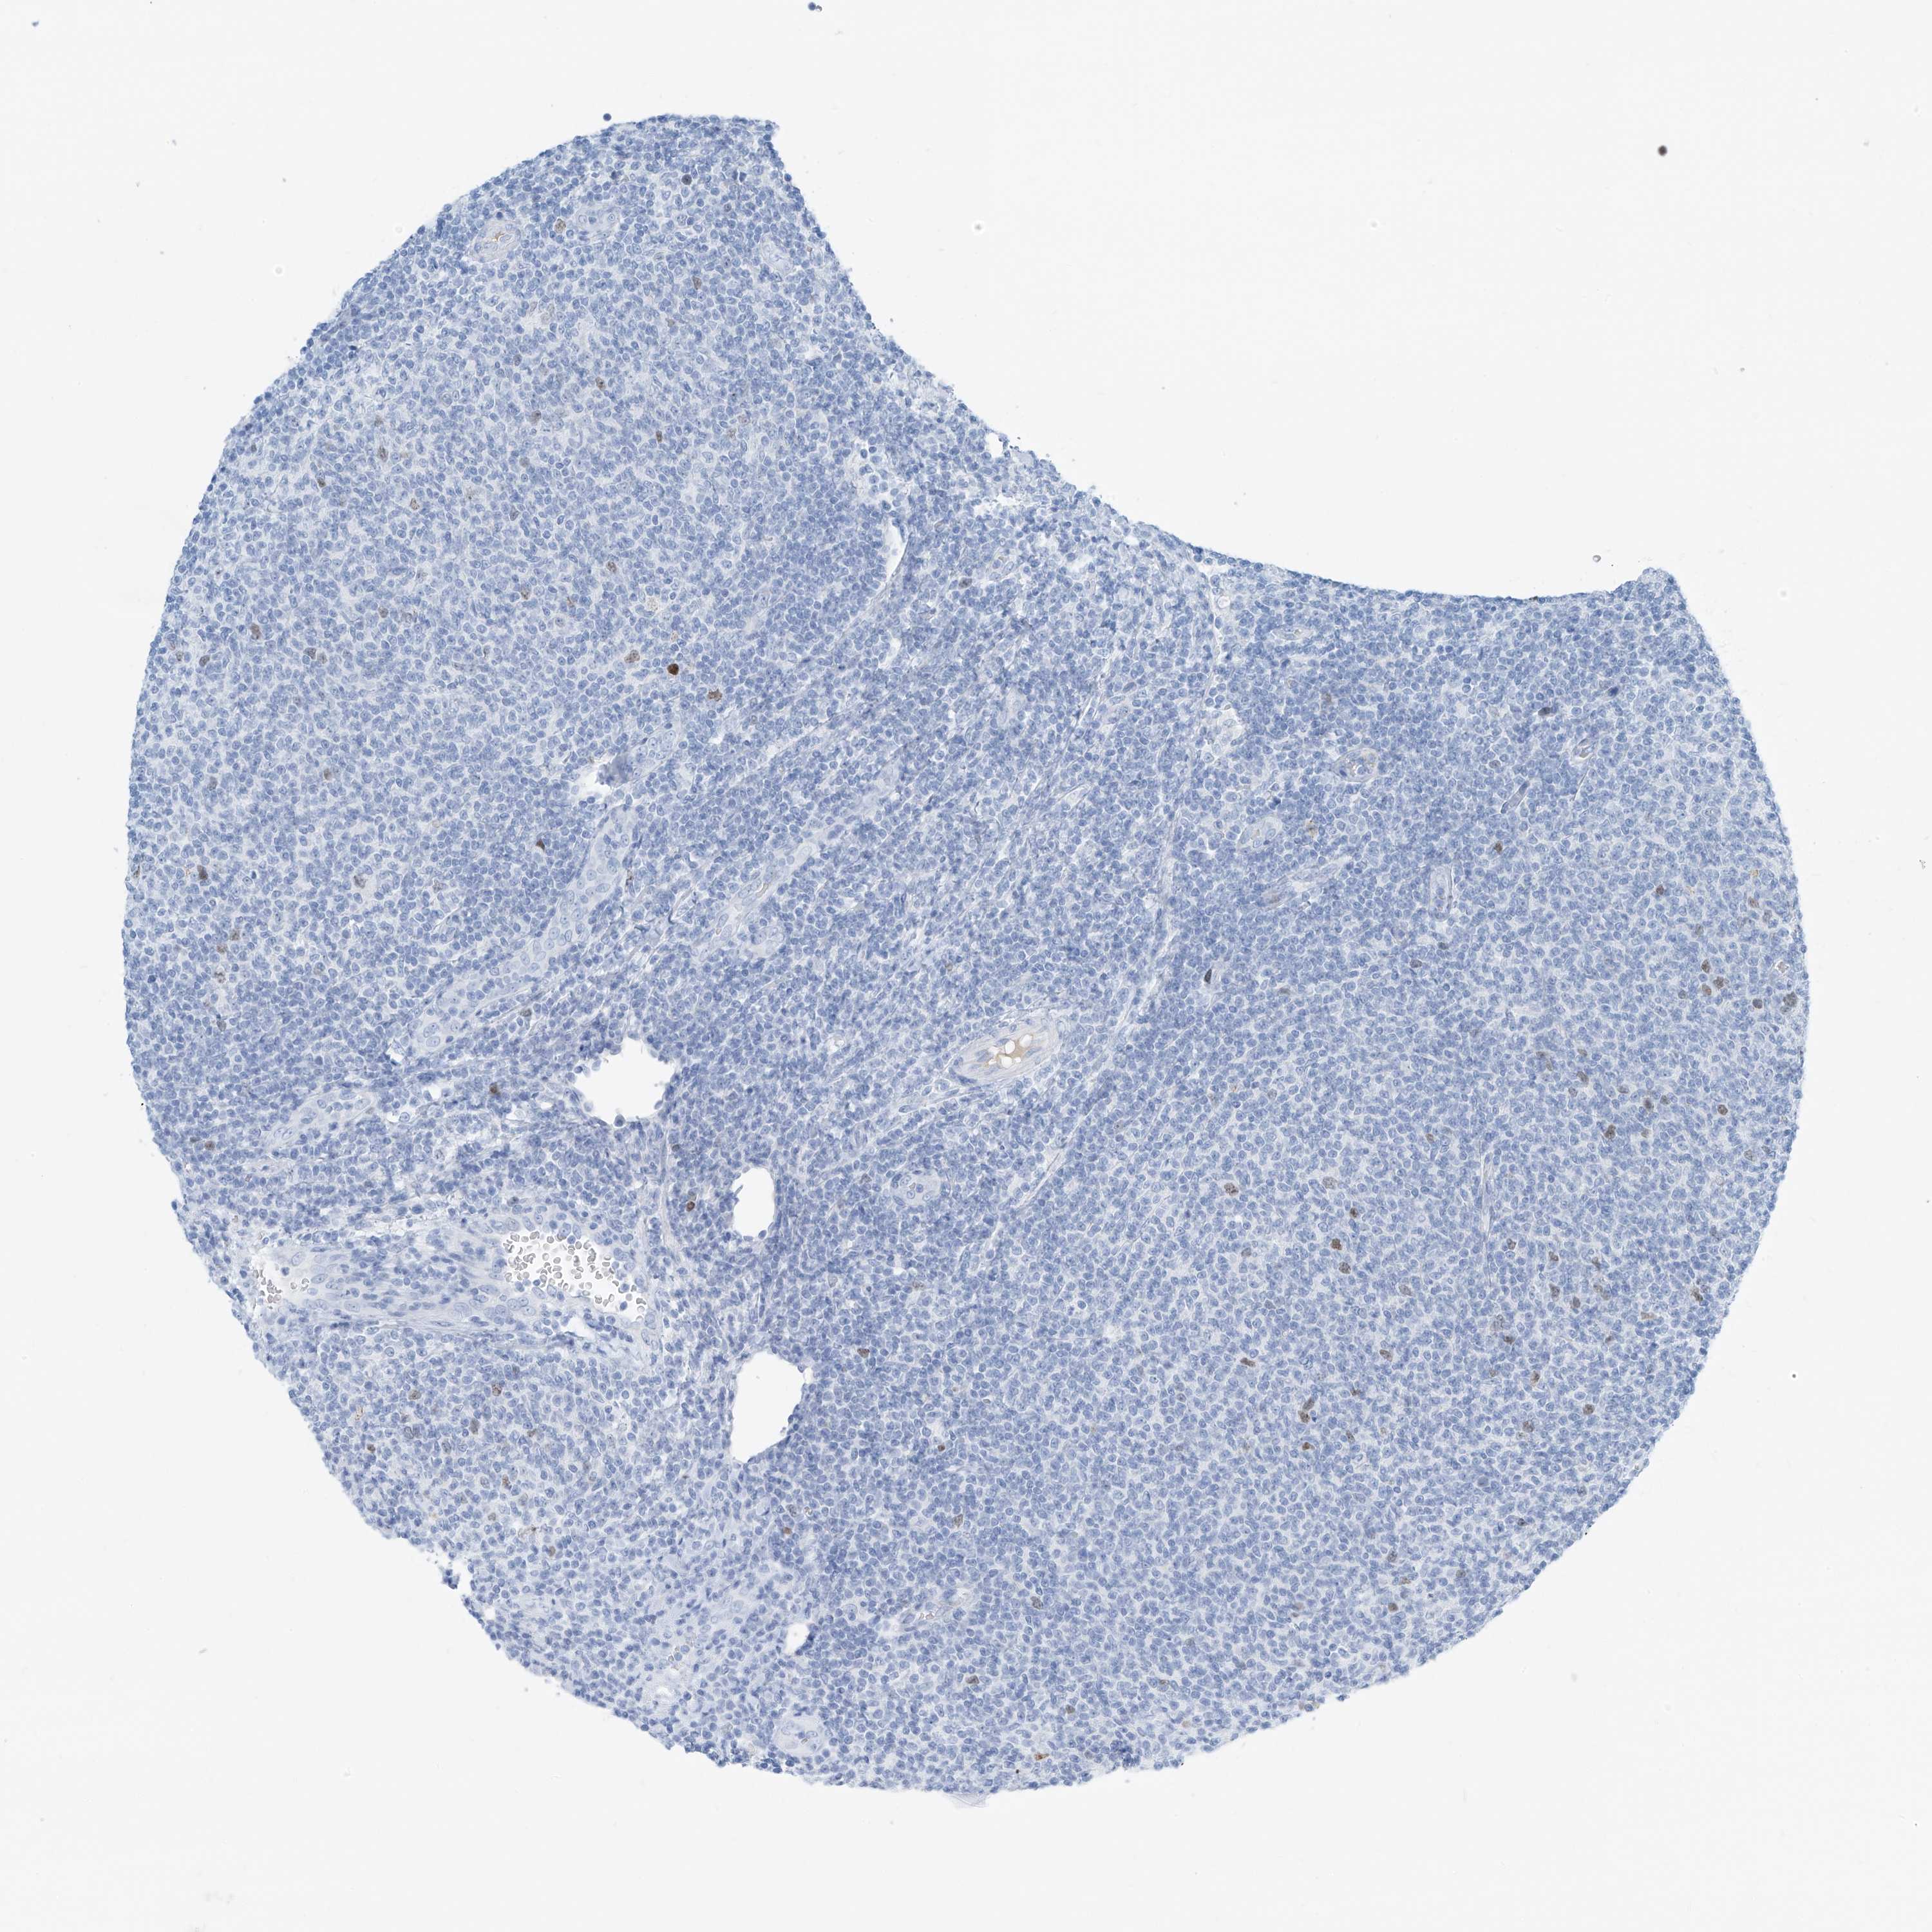

CANCER LYMPHOMA Show tissue menu

LYMPHOMA - Protein expressioni

A mouse-over function shows sample information and annotation data. Click on an image to view it in a full screen mode. Samples can be filtered based on level of antibody staining by selecting one or several of the following categories: high, medium, low and not detected. The assay and annotation is described here.

Each image is clickable and will lead to virtual microscopy that enables deeper exploration of all samples and also displays staining intensity scores, fraction scores and subcellular localization as well as patient and tissue information for each sample.

Antibody HPA035163

Staining

High

Medium

Low

Not detected

Intensity

Strong

Moderate

Weak

Negative

Quantity

>75%

75%-25%

<25%

None

Location

Nuclear

Cytoplasmic/membranous

Cytoplasmic/membranous,nuclear

Hodgkin's disease, NOS

Malignant lymphoma, non-Hodgkin's type, High grade

Malignant lymphoma, non-Hodgkin's type, Low grade